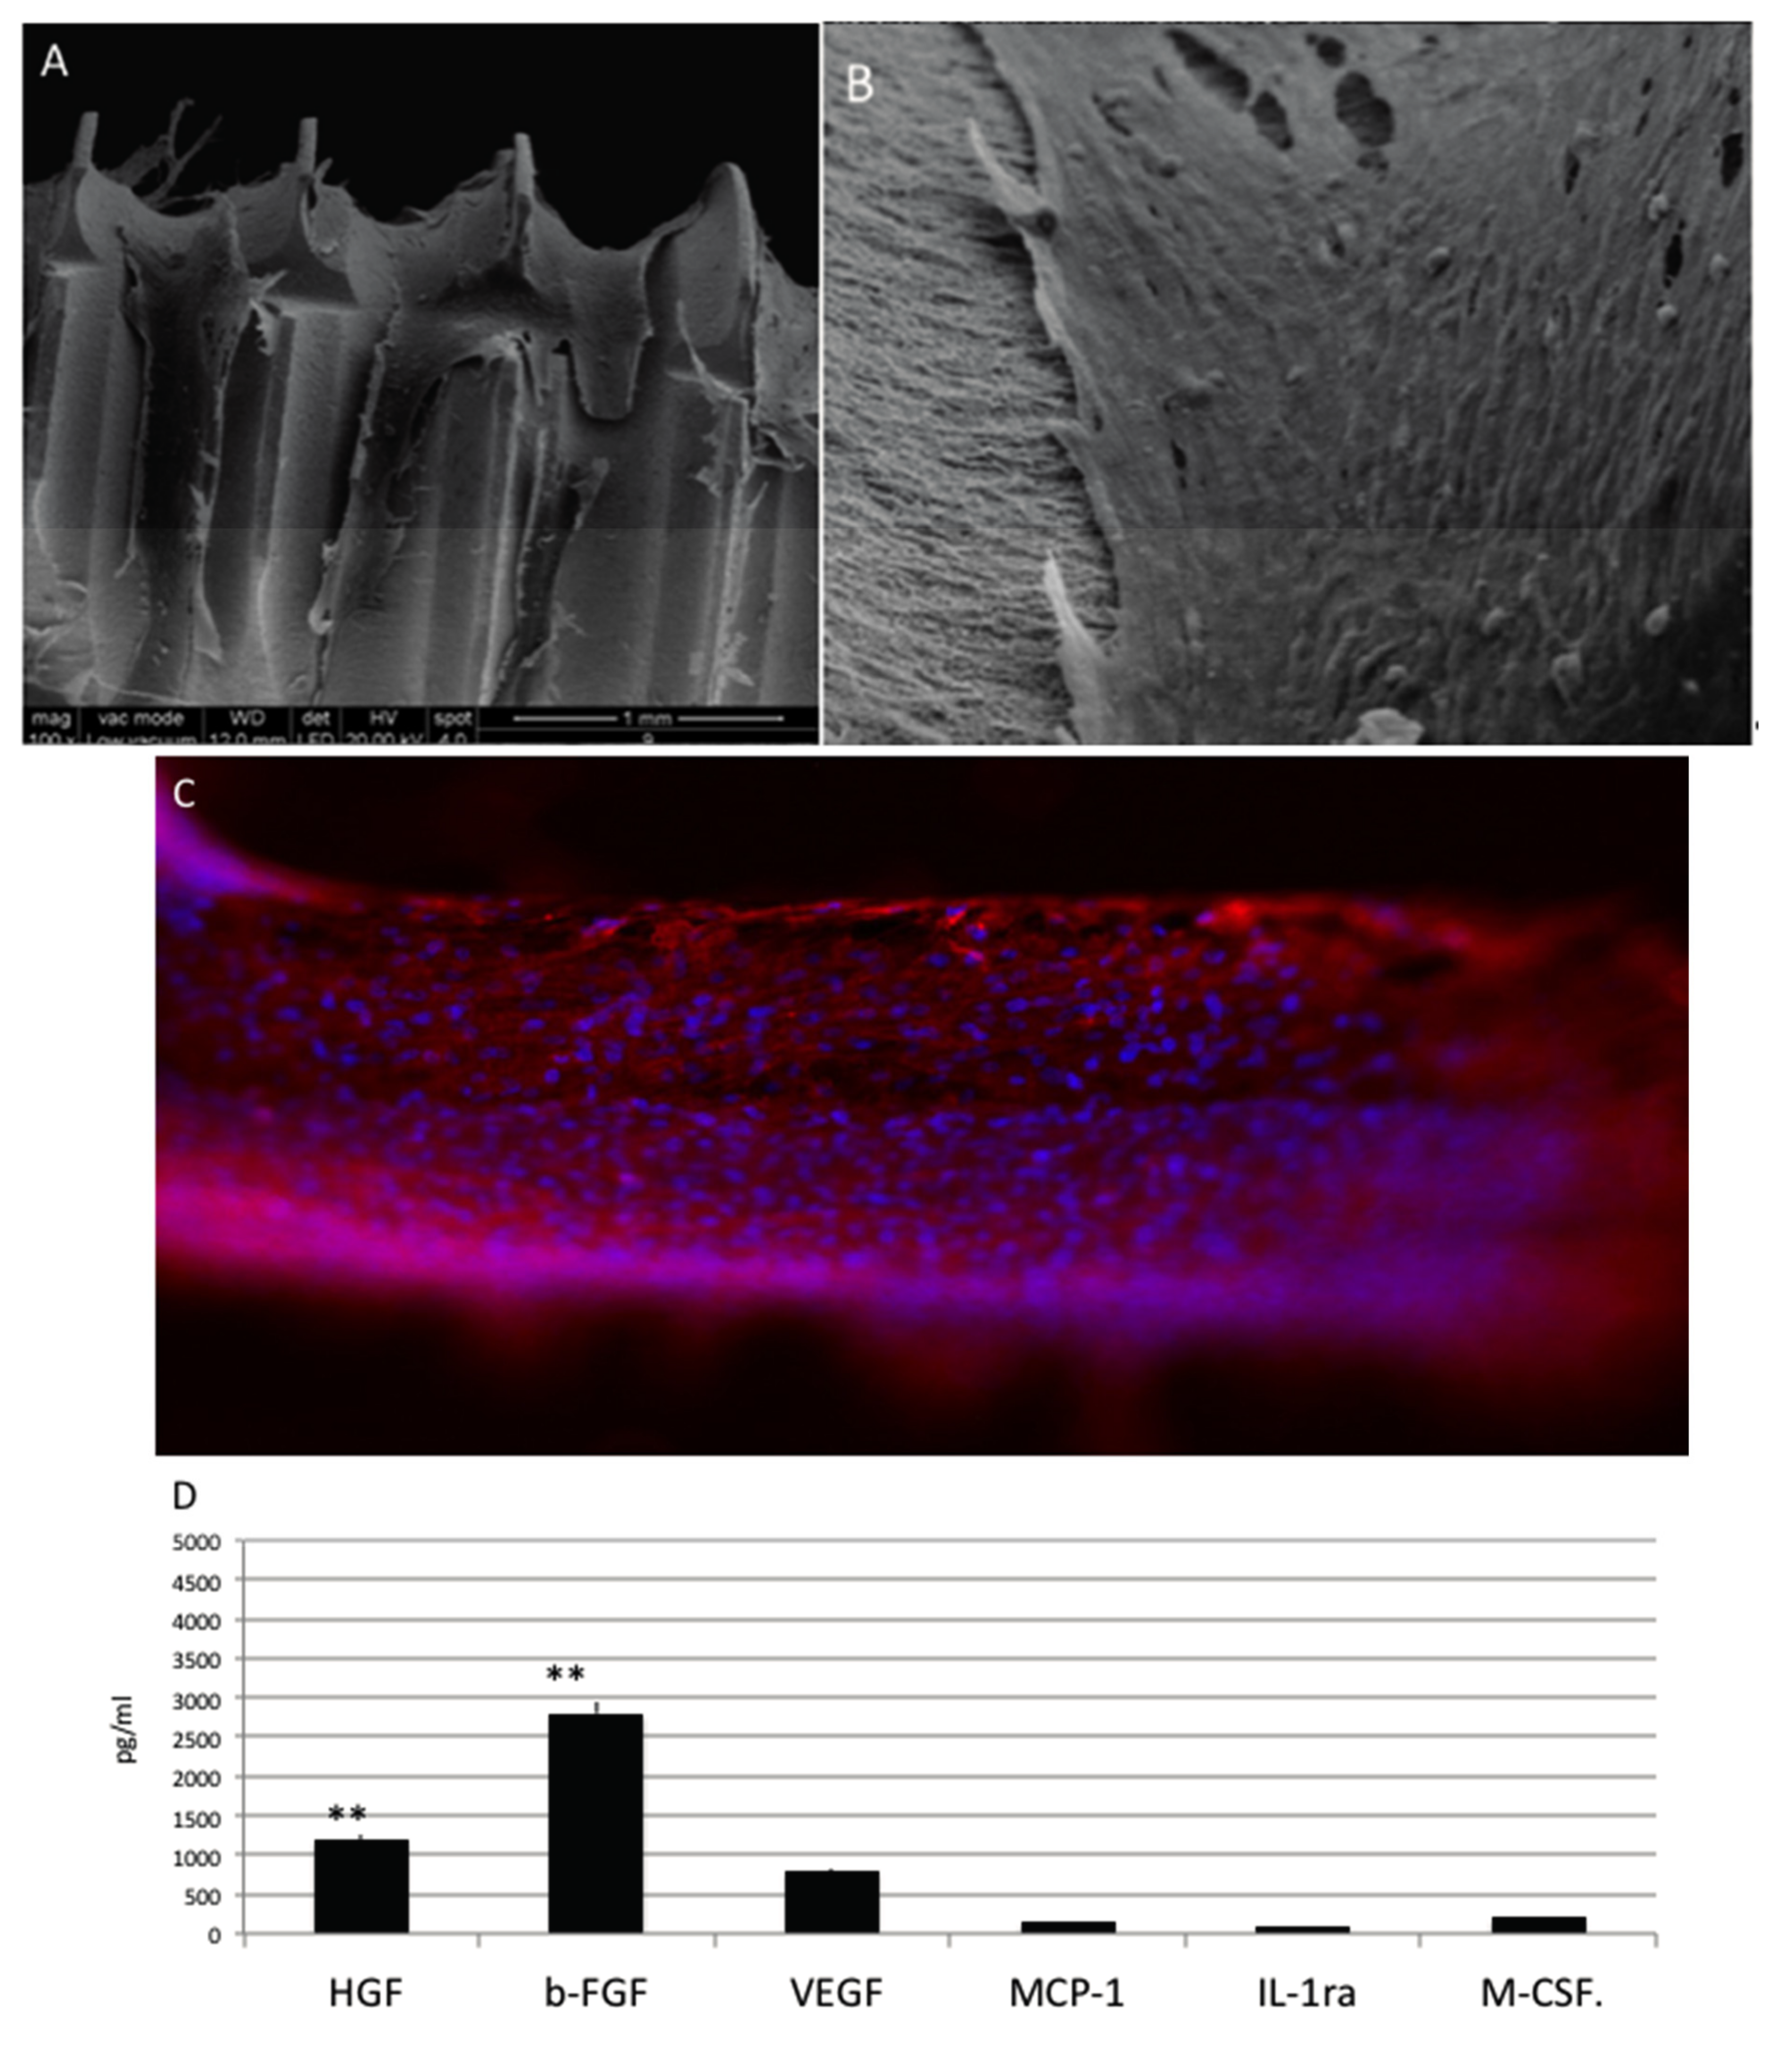

When MSC are cultured into osteogenesis medium are able to attach into all the surfaces as electro-microscopy (Figure 3A) and immunoistochemical analyses for phalloidine (Figure 3B in red) analyses confirm. Cell spread well and colonized all the surface. Well-defined phyllopodia, ensuring the attached, are well evident by the positivity for phalloidin (in red. Figure 3B) shows.

Figure 3.

(A) SEM analyses of MSC in presence of osteoinductive medium cultured onto OGI surfaces; (B) immunohistochemical test against phalloidine (red) (C) Quantification of growth factor release pg/mL. Statistically significant differences are indicated as ** p < 0.01.

To assess differences between HUVEC, MSC and osteoblastic like cells regarding the release of paracrine factors with several supportive effects such as antiapoptotic, immunomodulatory, antifibrotic, angiogenic, chemoattractive, and hematopoiesis, the following factors were quantified: Hepatocyte growth factor (HGF), basic fibroblast growth factor (b-FGF), vascular endothelial growth factor (VEGF), monocyte chemotactic protein-1 (MCP-1), stromal cell-derived factor 1-alpha (SDF-1a), interleukin 1 receptor antagonist (IL-1ra) and macrophage colony-stimulating factor (M-CSF) (Figure 3C). In this cells cultures, lower factors related to endothelial phenotype such as VEGF and bFGF, whether typical markers of osteoblast such as Hepatocyte growth factor (HGF) and colony stimulating factor 1 (M-CSF), are significantly expressed.

Cells of mesenchymal origin, and osteoblasts/osteocytes and bone marrow stromal cells originate from mesenchymal cells are able to mainly produce HGF. M-CSF is released by osteoblasts and exerts effects on osteoclasts thank to its paracrine effect. M-CSF binds to receptors on osteoclasts are able to induce differentiation, and to lead the increasing of plasma calcium levels.